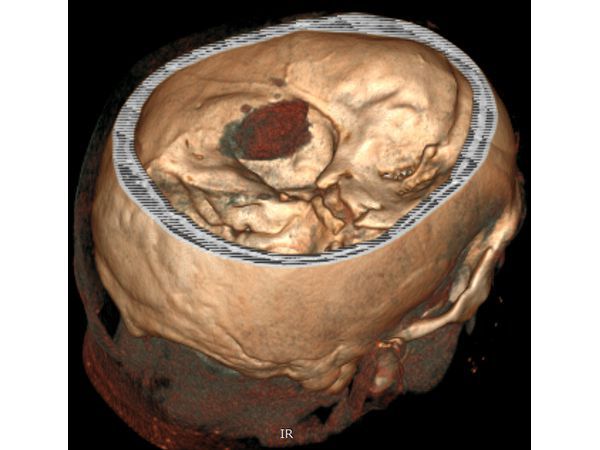

На следующий день пациенту выполнена краниотомия (трепанация черепа) и удаление инсульт-гематомы:

⠀• выполнен линейный разрез мягких тканей в левой височной области 5,0 см, скелетирована кость;

⠀• наложены три фрезевых отверстия, из которых резекционно сформировано трепанационное окно диаметром 3,5 см;

На следующий день после операции выполнен КТ-контроль: в области трепанации черепа видны костные фрагменты — костная стружка, уложенная в трепанационное окно при закрытии раны.